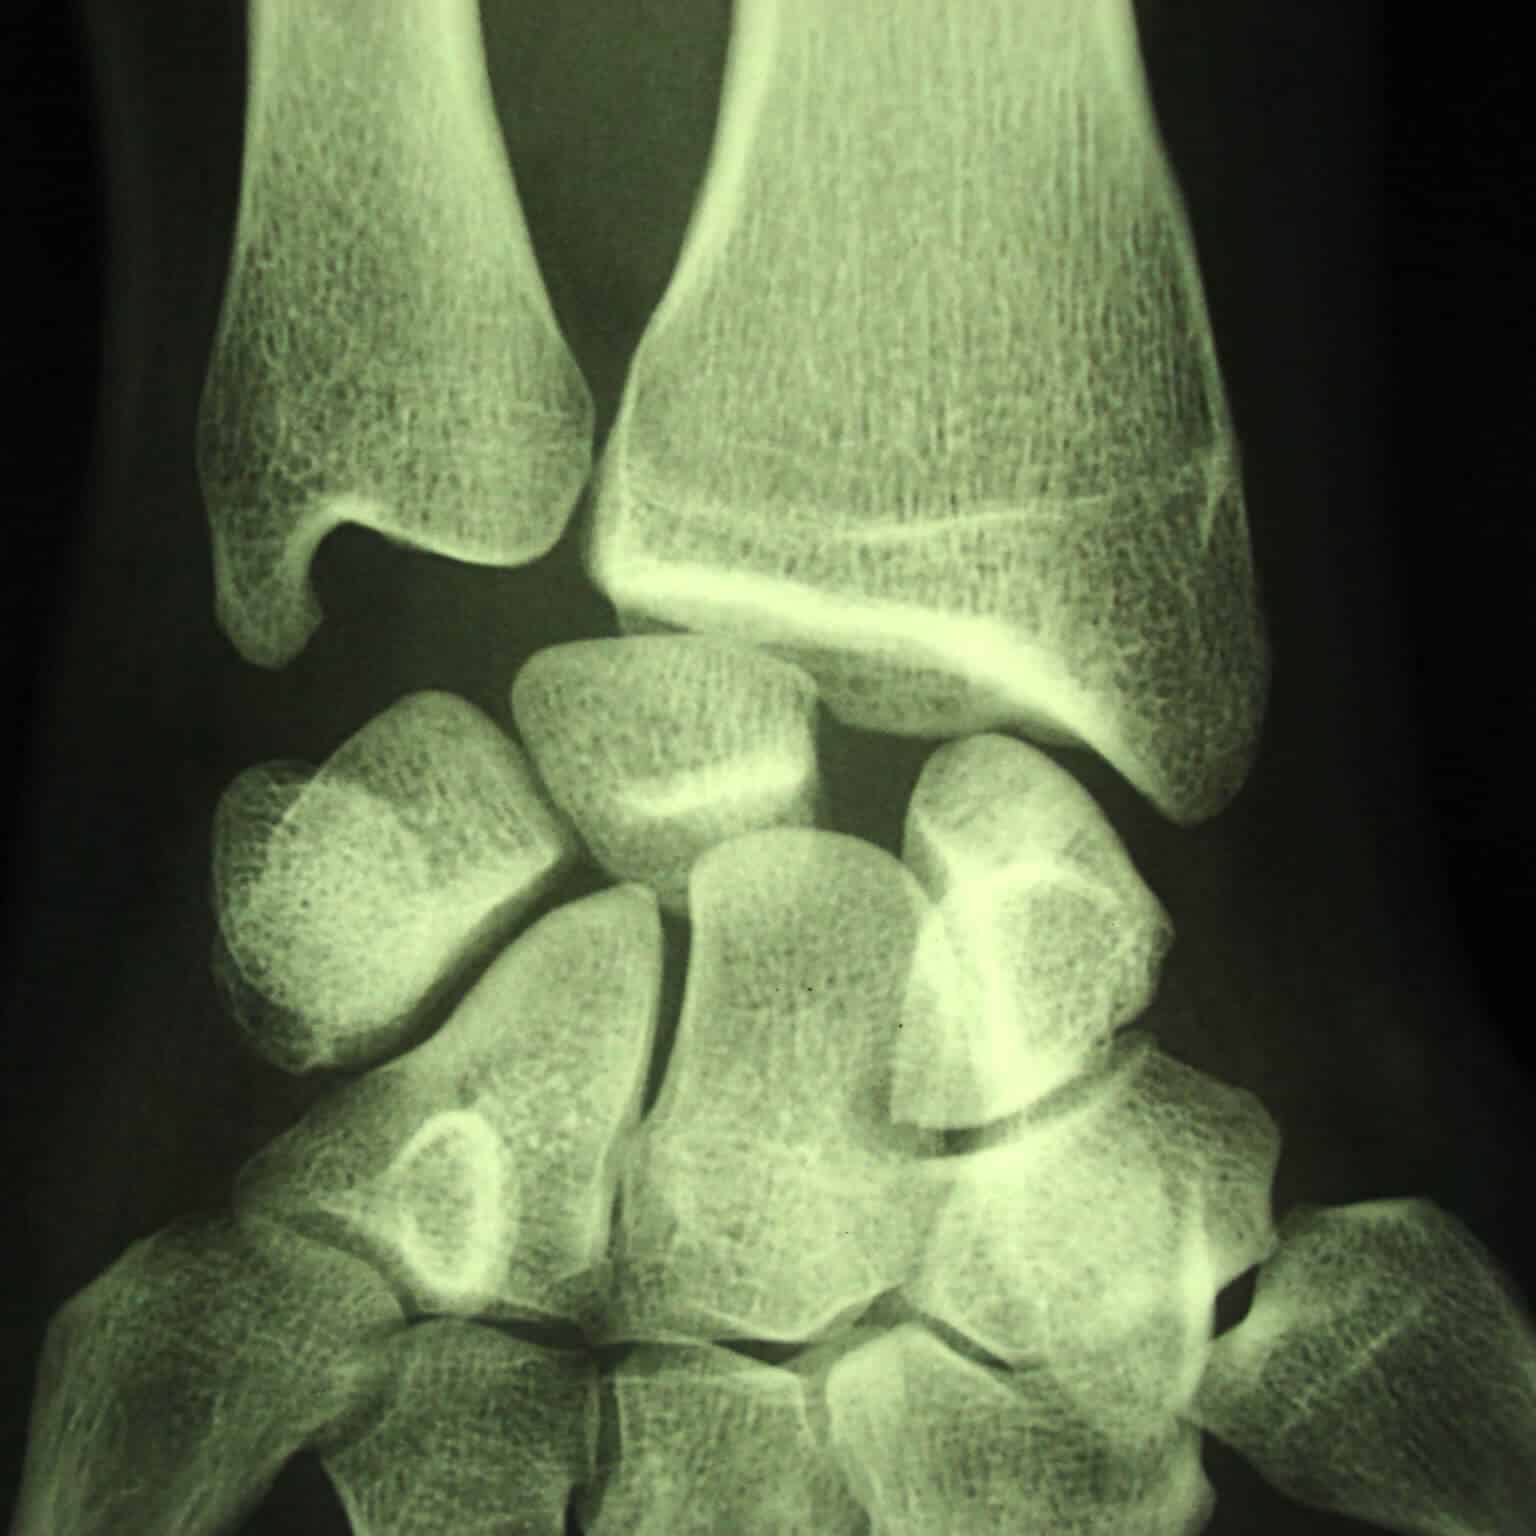

radio entorse luxation premiere rangee os carpe

Dislocation complète du carpe avec luxation de la première rangée avec rupture ligamentaire

Les lésions ligamentaires les plus sévères sont intracarpiennes. Elles nécessitent parfois des chirurgies longues et entraînent des raideurs importantes. Lorsqu’elles sont négligées, ces lésions peuvent évoluer vers des arthroses sévères du poignet.